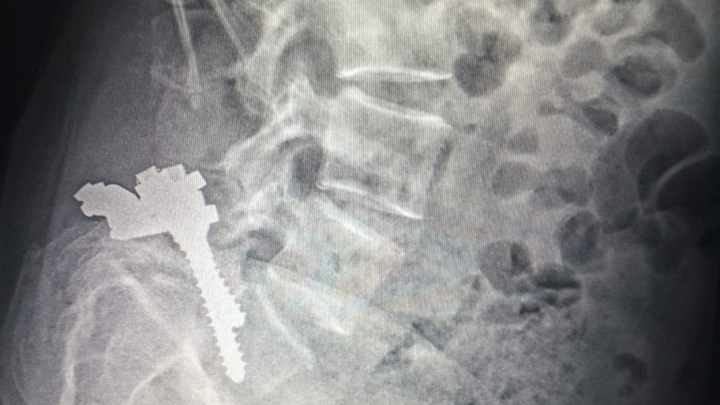

Hace 28 años, mi mamá fue operada de la columna y le colocaron prótesis de metal que, con el paso del tiempo, dejaron de ser funcionales. En los últimos meses, su condición ha empeorado: presenta dolor constante, adormecimiento en las piernas, mareos y una dificultad cada vez mayor para caminar, sentarse y descansar.